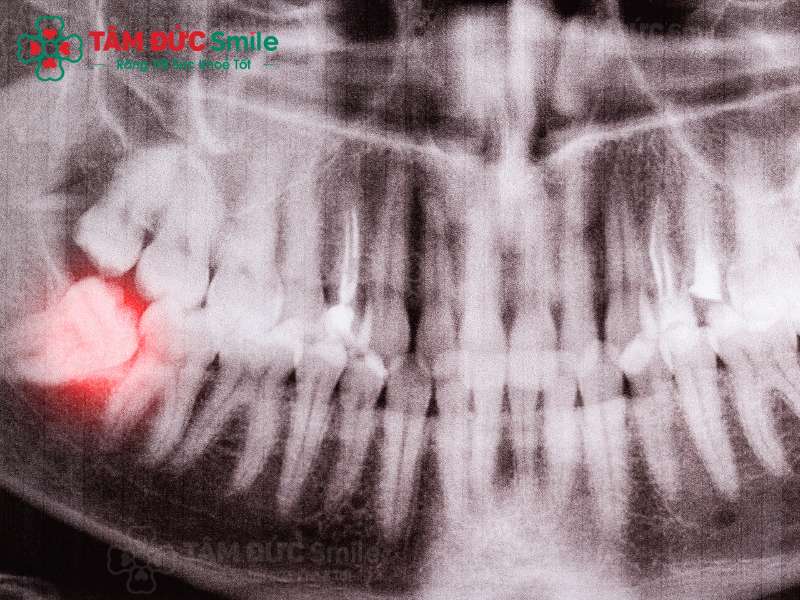

ảnh chụp mọc răng khôn bị sưng nướu

Răng khôn mọc lệch là một nguyên nhân gây sưng nướu thường gặp

Nguyên nhân chính làm nướu bị sưng trong khi răng khôn mọc là vì răng khôn chỉ mọc một phần. Răng khôn nhô lên một phần trên nướu và sau đó răng khôn mọc lệch, đâm vào kế cận gây viêm nướu. Ngoài ra, còn có những yếu tố khác làm tăng nguy cơ sưng nướu khi mọc răng khôn như: